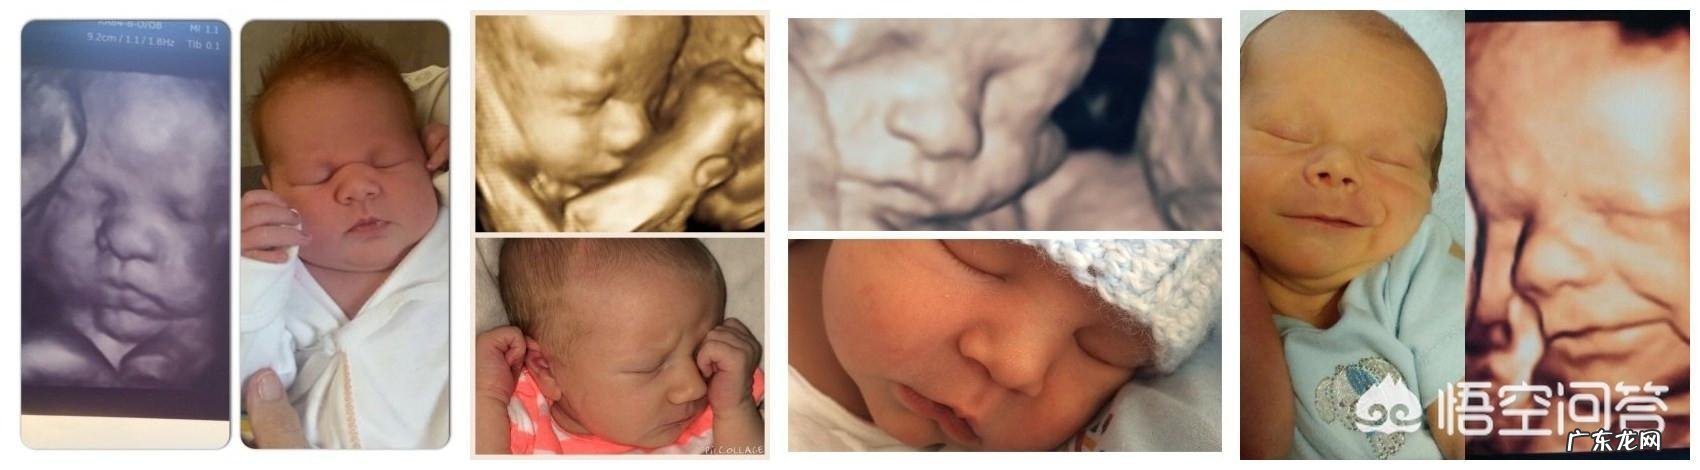

2.相貌很相似的情况 。

如果四维拍照时,胎儿比较配合或在睡觉,那么四维照片跟宝宝出生后照片就很相似,有些简直就是一模一样 。

3.相貌会随着年龄增长而变化 。

新生儿出生后皮肤都是皱皱巴巴的,脸蛋瘦瘦的,等宝宝的脸庞慢慢长开了,就会变得越来越好看了 。